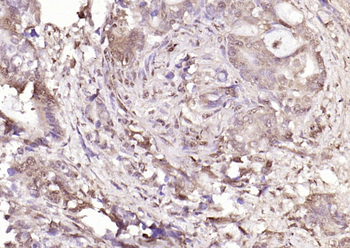

50 μl, 100 μl - MARK3 Recombinant Rabbit Monoclonal Antibody [orb704310]Featured

ICC, IF, IHC-Fr, IHC-P

Human, Mouse

Rat

Rabbit

Recombinant

Unconjugated

50 μl, 100 μl - Featured